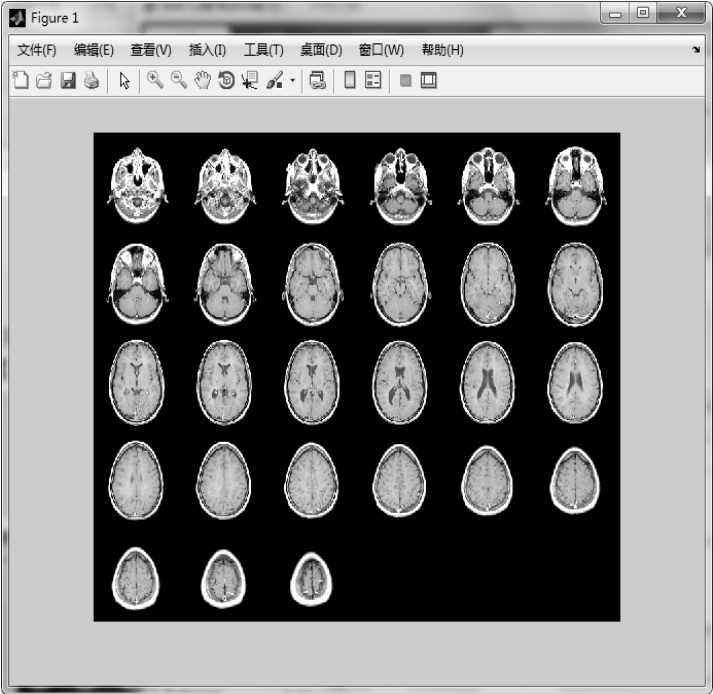

【实例3】 首先显示完整的多帧图像,然后显示前9帧图像。

图1.20 显示完整的图像序列

图1.21 显示图1.20中前9帧图像序列